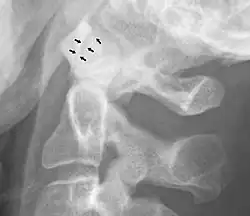

Ampliación anormal

Un ensanchamiento de la articulación atlanto-axial, medido entre la superficie posterior del arco anterior del atlas y la parte anterior de la apófisis odontoides, indica una lesión del ligamento atlantal transverso.[5] Normalmente, esta distancia atlanto-axial es inferior a 2 mm, a veces se acepta un máximo de 3 mm en los hombres y 2,5 mm en las mujeres.[5]